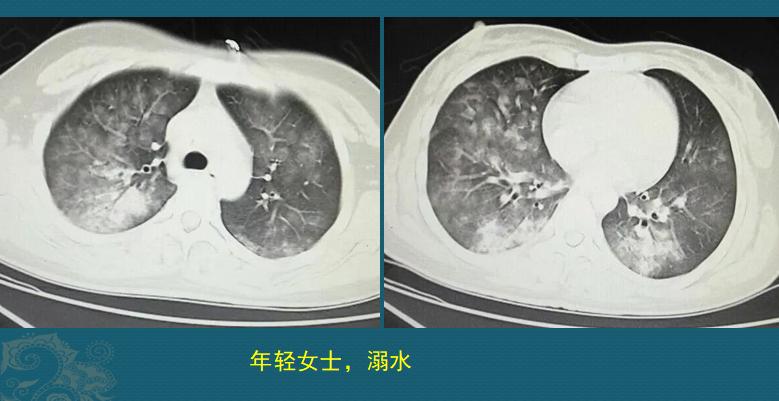

这是一位26岁女士,在人工湖游泳时溺水昏迷,呼吸、心跳停止,幸好被救生员及时发现,马上进行心肺复苏,呼吸心跳恢复,尽快送到医院,急诊CT发现双肺多发磨玻璃影,沿气道分布,部分肺实变(约溺水后2小时):

这是溺水性肺水CT肿的典型表现,形成原因主要是肺水肿和肺泡损伤:

抢救溺水患者,时间就是生命!多亏救生员急救措施合理,时间没有耽搁,住院后经过吸氧、祛痰、消炎、保肝等治疗后很快好转,没有留下后遗症!上图是她住院第3天复查的CT,肺部磨玻璃影以一种很快的速度吸收了。